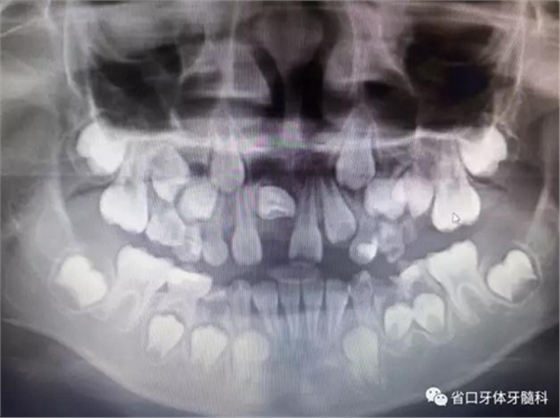

X線檢查:全景片

CBCT顯示右上中切牙埋伏阻生,牙軸呈水平位,冠向唇側(cè)、

根向腭側(cè),與鄰牙成90°夾角,牙根尚未發(fā)育完成,根端輕微彎曲。

診斷:11水平埋伏阻生。